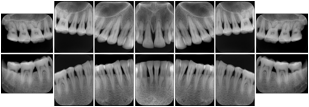

In most standard cases, images are oriented in structured layouts. These structured displays are useful to be shared between providers for reference purposes.

Table OO.1.1-1 shows structured display standard templates, where Viewset ID is based on the Japanese Society for Oral and Maxillofacial Radiology (JSOMR) classification provided by JIRA (Japan Medical Imaging and Radiological Systems Industries Association, www.jira-net.or.jp). Expected or typical teeth to be imaged location, region and designation codes are based on ISO 3950-2010, Dentistry - Designation system for teeth and areas of the oral cavity. For all the hanging protocols listed in OO.1.1-1, the value to use for Hanging Protocol Creator (0072,0008) is "JSOMR" and the value to use for Hanging Protocol Name (0072,0002) does not include "JSOMR" (e.g., "DL-S001A", not "JSOMR DL-S001A").

Table OO.1.1-1. Hanging Protocol Names for Dental Image Layout based on JSOMR classification